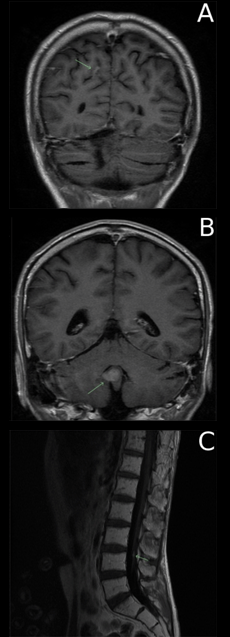

Eight years after his diagnosis, the patient developed asymptomatic intracranial disease with recurrent lesions in the septum pellucidum and inferior cerebellar vermis and also a ‘drop metastasis’ in the lumbar spine (Figure 1). Following discussion with his oncologist and a transplant physician, it was recommended that he receive high-dose chemotherapy and autologous hematopoietic stem cell rescue as this would provide the highest likelihood of remission and cure. To the surprise (and dismay) of his treating team however, he declined active treatment including options such as clinical trials— believing that prayer (he was a devout Protestant) would heal his disease. He was completely competent and remained very clear about his reason for refusing medical treatment. He was not depressed or anxious (about his disease, the toxicity of treatment and his future) and remained calm and considered during all discussions. Discussions were held between the patient and his oncologist, transplant physician and palliative care physician. Unfortunately, while he remained resolute, he gradually developed progressive neurological symptoms with ataxia, recurrent seizures and diplopia. With serial imaging demonstrating progressive disease, he eventually died in a palliative care unit 18 months after recurrence.

Figure 1: Magnetic resonance scan showing recurrent lesions in the (A) Septum pellucidum, (B) Cerebellar vermis, and (C) Lumbar spine.